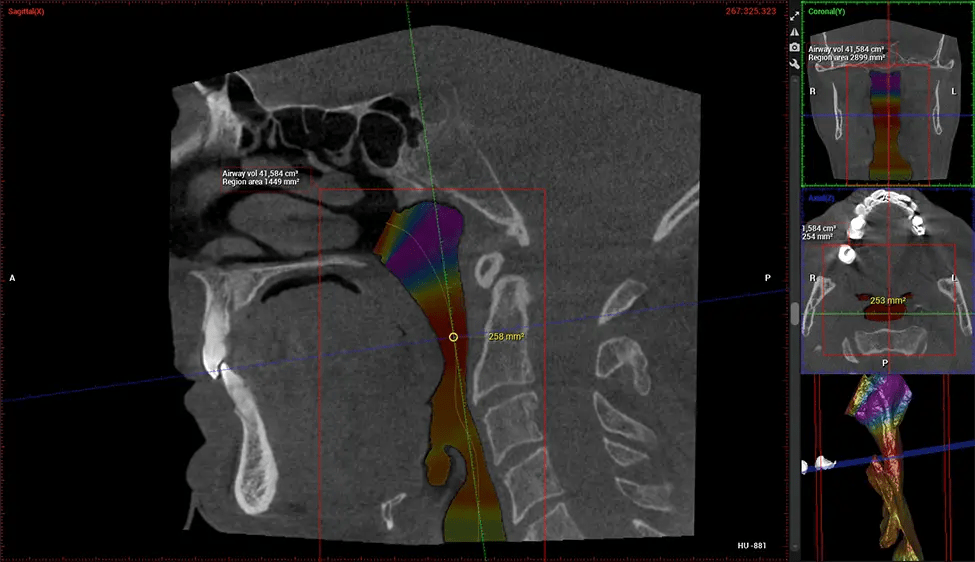

This 3D scan, called cone beam computed tomography, gives your dentist a more complete image of your oral anatomy and disease processes than a traditional X-ray. Unlike conventional X-rays, which capture a 2D image of your mouth from various angles, a 3D scan takes multiple digital X-rays for one image. It provides a complete view of your jaw, teeth, nerves, and soft tissues. This enhanced view allows dentists to detect minor issues not visible in traditional 2D scans, such as impacted wisdom teeth or bone fractures in the sinus cavity.

There are many benefits to using CBCT technology, especially compared to the traditional 2D X-ray format. One of the most significant advantages of CBCT scans is that they provide much more information than traditional X-rays. A scan lets your dentist see images from all angles of your jaw and mouth, including your sinuses, nasal cavity, cheekbones, and other surrounding areas. This added information helps your dentist craft a comprehensive treatment plan that addresses all aspects of your oral health.

Planmeca Viso G7 CBCT ( Cone Beam CT Scan ) is designed to surpass the demands of industry leaders, specialists, and large institutions. It’s has a large ø25×30 cm sensor with four built-in cameras. It can capture unlimited volume sizes from a ø3×3 cm to a ø30x30cm volume capturing the skullcap through C7 on the cervical spine. The Planmeca Viso G7 offers the industry’s largest single volume scan of ø30×19 cm. It’s poised to handle advanced imaging modalities such as Planmeca ProFace® and Planmeca 4D™ Jaw Motion technology. The occipital head support allows an unimpeded view of facial tissue.

Planmeca is the only manufacturer clinically proven to dramatically reduce patient radiation without sacrificing image quality. Planmeca Ultra Low Dose™ achieves an average reduction in dose of 77% without a statistical reduction in image quality allowing doctors to incorporate 3D imaging into routine protocols with effective patient radiation often lower than 2D intraoral imaging. This increases patient care, allows doctors to diagnose more dentistry, and often earlier in disease progression, than with 2D imaging alone.